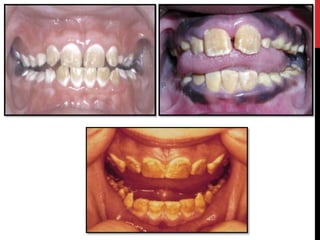

Hypoplastic amelogenesis imperfecta:

Basic alteration centers on inadequate deposition of enamel matrix.

• Generalized pattern

• Localized pattern

• Autosomal dominant smooth pattern

• X- linked smooth pattern

• X-linked rough pattern

Hypomaturation amelogenesis imperfecta

 Enamel matrix is laid down appropriately & begins to mineralize.

 There is defect in maturation of enamel crystal structure.

• Pigmented pattern

• X linked pattern

• Snow-capped pattern

Hypocalcified amelogenesis imperfecta

 Enamel matrix is laid down properly but no significant

mineralization occur.